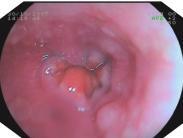

• 氣管狹窄

氣管狹窄病因有先天性(如氣管發(fā)育異常)和后天性,如各種炎癥或創(chuàng)傷后的疤痕狹窄、氣管周圍腫物(如甲狀腺腫物)的長期壓迫,使氣管壁軟化而狹窄;氣管切開或插管后的狹窄;因鄰...